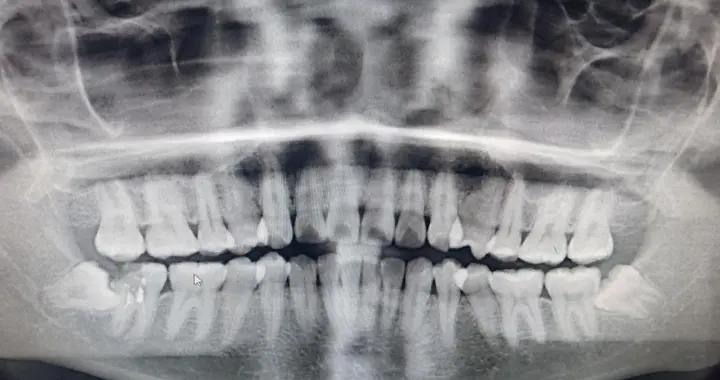

顱縫早閉的診斷標準從兩方面來看:一方面是臨牀上的表現即頭型的異常,但是這個頭型的異常需要由神經外科的醫生來判斷;第二個就是可以摸到明顯的一個鼓脊,那麼和這個頭型是相符合的,能夠摸到可能閉合的這條骨縫上的鼓脊,這一個是症狀。再一個非常重要的客觀的檢查就是3D的顱骨CT的三維重建,在這個三維重建上可清晰地看到哪些骨縫是正常的,哪些骨縫是提前閉合的,和臨牀表現能夠對的上,基本上就可以做出一個明確的診斷。

目前我科有3例顱縫早閉(矢狀縫早閉),待手術進行,讓我們爲患兒加油